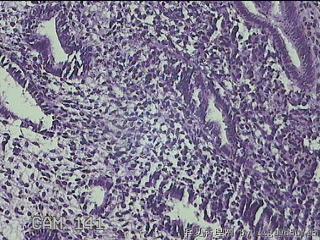

子宫腔内容物

性别

女

年龄

31

临床诊断

宫腔息肉?

一般病史

宫内异常回声2月余。

标本名称

大体所见

灰白暗红色不规则碎组织2x1.7x0.3cm一堆.

图14

采低倍